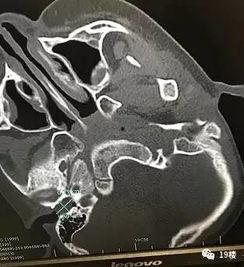

2. 科普型:一些医学专家或耳科医生会通过超大耳屎视频,向大家普及耳朵健康知识,提醒大家注意耳朵卫生。